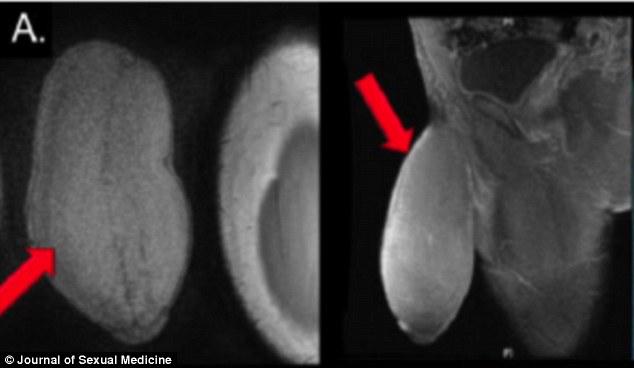

---Primo intervento di riduzione del pene del mondo eseguito in Florida.